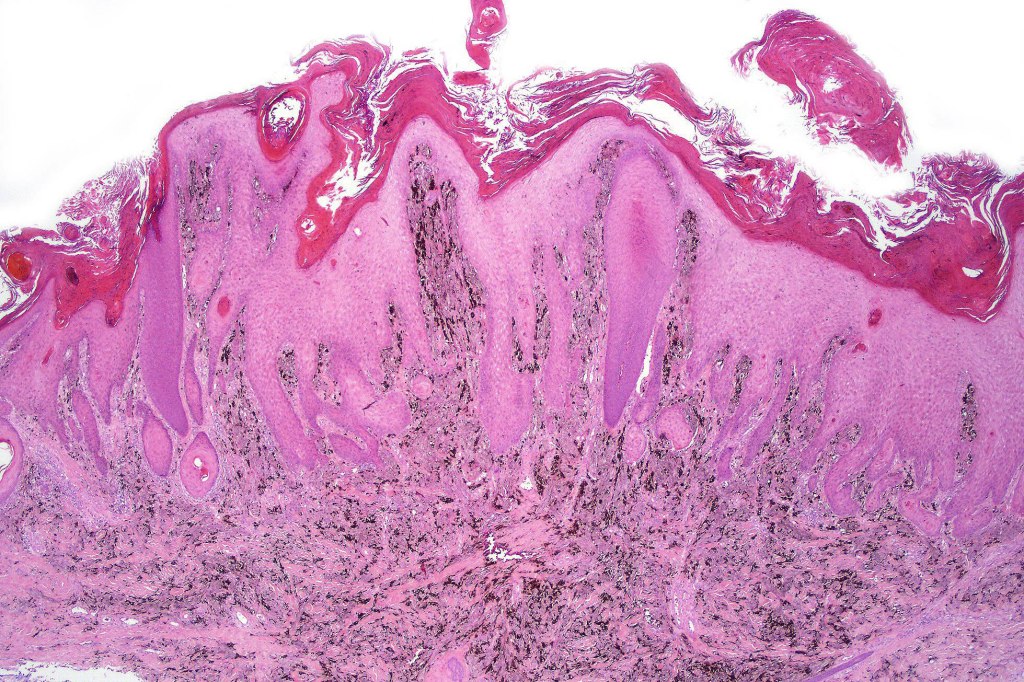

•Wedge shape or less often plaque like silhouette

•Commonly associated with marked acanthosis/pseudoepitheliomatous hyperplasia although much less commonly, the epidermis is strteched over the lesion